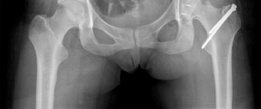

We review everything you need to understand about Open Hip Dislocation: How Fascia Lata Autograft Restores Stability. A 25-year-old female with left hip posterior femoroacetabular impingement received treatment via surgical hip dislocation. The procedure involved posterior wall rim trimming and labral reconstruction using a fascia lata autograft. This intervention successfully addressed chronic posterior hip pain and associated labral pathology stemming from a prominent posterior acetabular wall.

Standard preoperative imaging must include an anteroposterior (AP) pelvis, cross-table lateral, and false-profile view of the affected hip. These evaluate for dysplasia, impingement morphology (cam/pincer), and degenerative changes.

Magnetic Resonance Arthrography (MRA) is the gold standard for evaluating the capsuloligamentous complex. Extravasation of contrast anteriorly often delineates the size and location of the capsular defect. MRA also assesses labral integrity, chondral damage, and the viability of the femoral head. A 3D computed tomography (CT) scan is highly recommended to quantify femoral anteversion and acetabular version, as unrecognized osseous malorientation (e.g., severe femoral retroversion) will predispose the reconstruction to failure if not addressed concurrently with a derotational osteotomy.